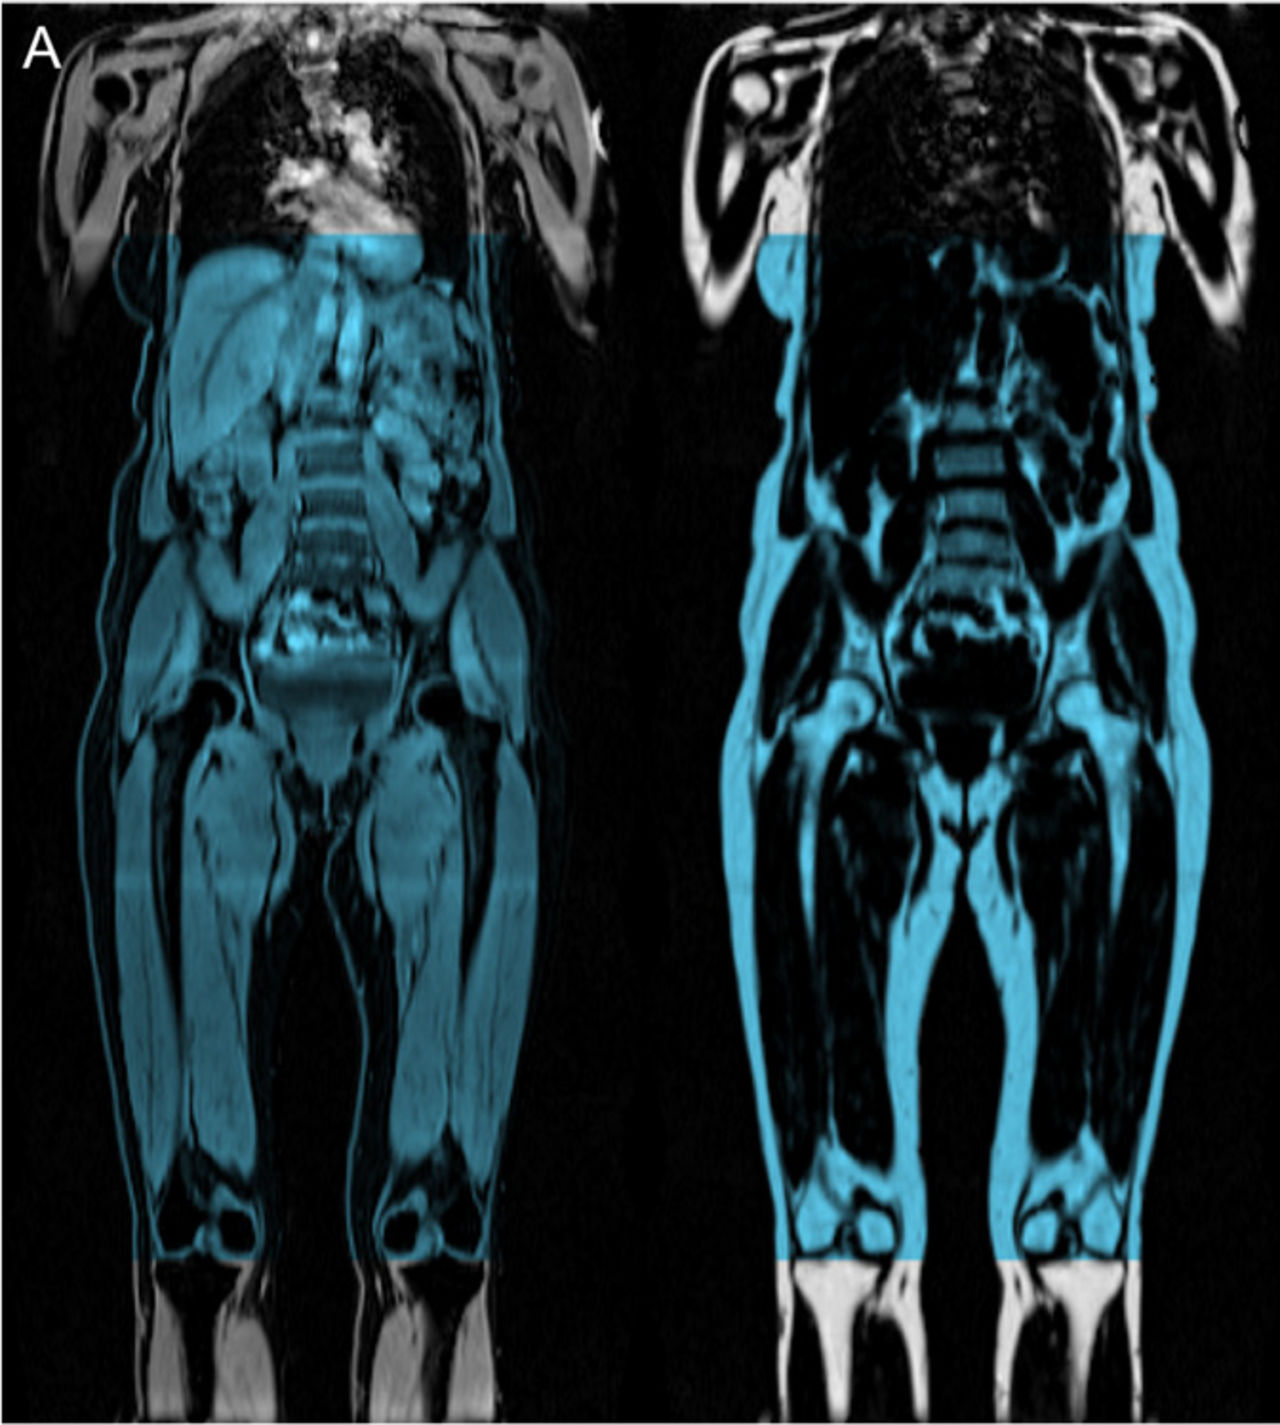

Metabolic risk related to body-fat accumulation is strongly dependent on fat distribution. Central obesity and, in particular, ectopic fat accumulation, are important metabolic risk factors. The only way to directly assess body-fat distribution is to use tomographic imaging techniques. This project has developed a method for quantitative assessment of body composition that measures both fat distribution and muscle volume.

The only way to directly assess body-fat distribution is to use tomographic imaging techniques. Magnetic resonance imaging (MRI) can also measure muscle volumes, muscle fat infiltration and other ectopic fat accumulation, which makes it a powerful tool for advanced body composition assessment.

To be able to measure fat accumulation in different parts of the abdomen an image analysis method was combined with knowledge in MR physics. The measurement technique has been refined and can now measure in more detail and larger parts of the body, fat infiltration in the muscles as well as muscle volume.

Copyright AMRA AB